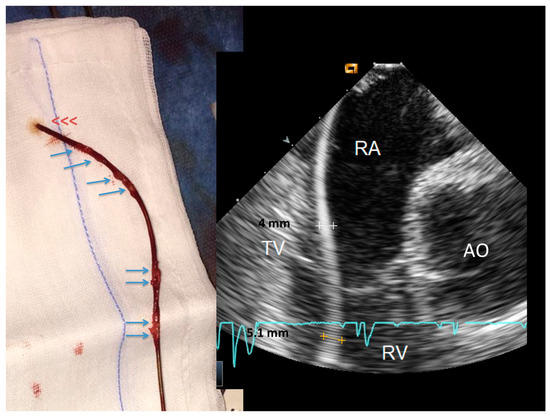

2.2.2. After the Extraction

3.2. Post-extraction ICE

4.2. Nature of the Ghost